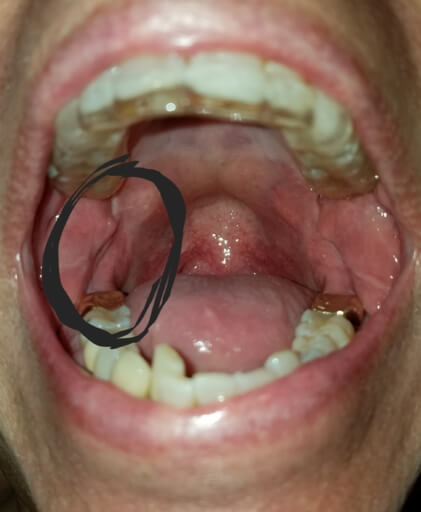

Hi, I have a frenulum on the right side of my mouth. It connects to my gums about 1cm behind the upper and lower back molars. It has become tight and painful. Have you ever seen anything like this? Is it safe to have it cut? I will attempt to add a photo. Thank you, H. Jay Graber

A frenum or frenulum is a small fold of tissue that restricts and secures the motion of a mobile organ. I have not heard of a frenulum in the back of the mouth. It would be best to bring this to the attention of your dentist, especially because it is causing discomfort. I did not see a picture attached to your question, however I am wondering if it is part of your cheek or possibly an impacted tooth that may be causing this discomfort. Use warm salt water rinses several times a day to soothe the tissues until you have a proper exam and diagnosis.

A frenulum or frenum is a small fold of tissue that restricts or secures the motion of a mobile organ. I have not seen a fold of tissue (unless sutured) that connects distal to the molars. There is a frenum that connects your tongue to the floor of your mouth as well as one that attaches your lips to your jaws. Since you are experiencing pain, it is important for you to see your dentist immediately to be sure you do not have an infection or a tooth that is creating swelling in the area.